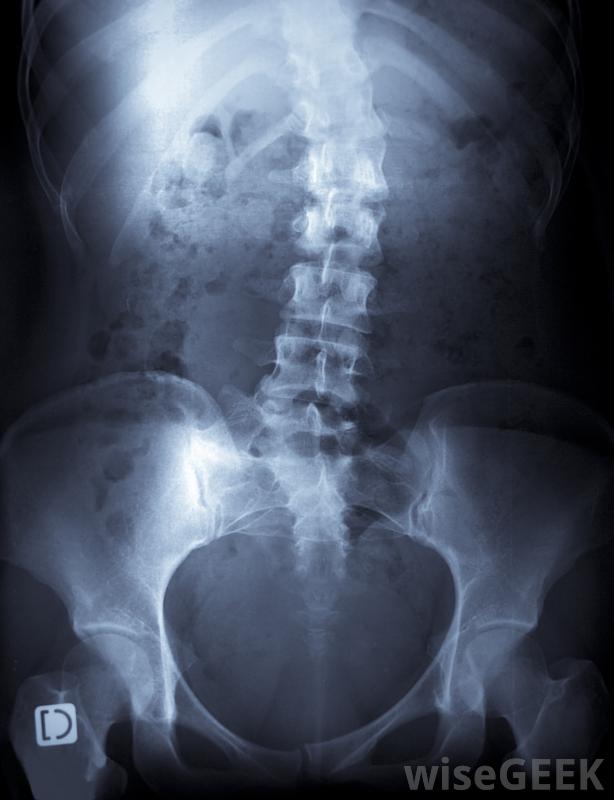

脊柱侧凸和椎管狭窄症是两种最常见的脊柱疾病,这两种疾病都可以通过各种药物治疗得到改善,其他脊椎疾病如坐骨神经痛和椎间盘突出症也可以治疗,然而,有时这些脊椎疾病如果得不到适当的治疗或护理,会变得相当严重并导致退行性变,有些脊椎疾病是由于不活动和静止不动而引起的。各种治疗方法,如脊柱锻炼和抗炎药可以帮助减轻疼痛,增加愈合,提高脊柱的柔韧性和强度。

椎间盘突出会导致背部腰部疼痛最常见的脊柱疾病或疾病见于许多青少年,被称为脊柱侧凸,它使脊柱扭曲到一个不自然的位置,导致姿势不好,背部受到压力。通常,脊柱侧凸是由于姿势不好或剧烈活动引起的,还有证据表明,脊柱侧凸也可能有遗传因素。如果不治疗,脊柱侧凸会使脊柱退化,导致腹部器官受压,导致疼痛,最终导致死亡。脊柱侧凸的治疗通常是在早期进行的,以防止这种情况的发生,包括戴一段时间的背托,以帮助脊椎伸直和正常发育

一个健康的脊柱和一个患有脊椎骨关节炎的例子。椎管狭窄症是其他脊椎疾病之一,它通过使腰椎部分变窄而对脊髓造成不必要的压力椎管狭窄的病因从先天缺陷到关节炎,如果不治疗,会变得非常虚弱。大多数椎管狭窄症的治疗方法都声称背痛不会完全消失,但是各种运动和生活方式的改变将有助于增强脊柱的强度和降低脊柱的强度疼痛的症状。一些医生可能会告诉病人脊柱手术来帮助恢复脊椎,然而,这些手术往往会带来各种各样的并发症。

脊柱侧凸,导致脊柱异常弯曲,是一种常见的脊柱疾病。